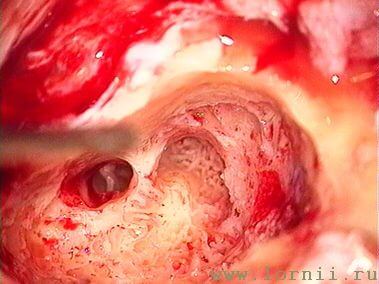

Борами выполнялась антромастоидотомия (рис. 7). Через заднюю тимпанотомию вскрывалась барабанная полость (должно быть хорошо обозримо наковально - стременное сочленение, длинный отросток наковальни и окно улитки), размеры отверстия тимпаностомы должны быть не менее 3-4 мм, для нормального прохождения катушки импланта (рис. 8).